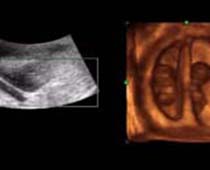

Clips vidéo 4D scan ultrason fœtal | Dr N Layyous

Clips vidéo 4D scan ultrason fœtal